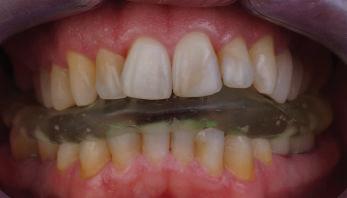

Dental Tribune Bulgarian Edition / октомври 2022 г. 23клиничен случай | ортодонтия реклама Лечението е продължило 21 месеца. Проведено е домашно избелване с индивидуални шини. За автора: Д-р Радой Димитров завършва с отличие Факултета по дентална медицина към МУ–София през 2015 г. В продължение на 5 години работи в няколко водещи практики в София, като през 2019 г. заедно със своята съпру га д-р Траяна Димитрова основават собствена практика в гр. Гоце Делчев –Dimitrovi Dental Care. Посещава редица курсове за повишаване на квалификаци ята, но най-сериозен тласък в развитието на ортодонтската си практика получава след завършването на комплексната ортодонтска програма, воде на от д-р Иван Горялов, базирана на дисциплината „Алекзандър“ – система с повече от 50 години опит в целия свят. Д-р Димитров е член на Българския изследователски клуб „Алекзандър“. Взе ма участие като гост-лектор в симпозиума с международно участие The Power of the Alexander Discipline, който се проведе на 14–15.05.2022 г. С д-р Ди митров можете да свържете на тел. +359885 252 025. Заключение Представеният случай е ярък пример за възможностите и красо тата на дисциплината „Алекзандър“ – приложен е утвърден под ход с ясни правила и са постигнати очакваните цели. Резулта тът ще бъде дългосрочно стабилен, тъй като са спазени всички правила, които се отнасят към максимално комфортната пози ция на зъбите в края на лечението. Постигнати са красива усмив ка и стабилна оклузия. ПОСТИГНАТИ РЕЗУЛТАТИ ОТ ЛЕЧЕНИЕТО 1. Коригирана ръбцова захапка 2. Коригирана клас 3 захапка в областта на ку чешките зъби 3. Коригирана кръстосана захапка в дисталните участъци 4. Коригиран овърджет и овърбайт 5. Разширена е горната зъбна дъга 6. Подредени зъби в горната и долната челюст 7. Постигната е стабилна захапка с множество контакти в ЦО 8. Драматично е подобрена дъвкателната функ ция 9. Подобрена е линията на усмивката ДРУГИ ПРОВЕДЕНИ ДЕНТАЛНИ ПРОЦЕДУРИ 1. Домашно избелване на зъбите 2. Екстракция на мъдреците Фиг. 12a Фиг. 12b Фиг. 12c Фиг. 12eФиг. 12d Фиг. 12f Фиг. 12g Информация за дати, цени и отстъпки www.bracescourses.com 0889 22 55 01 Практически курсове лектор д-р Иван Горялов Дисциплината „Алекзандър“ ПЪТЯТ КЪМ СУПЕРУСМИВКИТЕ 100% връщане на цялата сума, ако не сте удовлетворени след преминаване на Ниво 1 Директно и индиректно залепяне на брекети Анализ, диагноза и план на лечение Лечение на клас 2 дълбока захапка Екстракционно лечение Лечение на клас 3 отворена захапка НИВО 5НИВО 1 НИВО 2 НИВО 3 НИВО 4